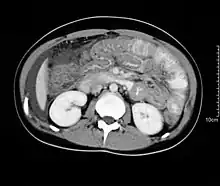

| H&E Stain: Dense Eosinophilic infiltration of gastro-duodenal wall | |

Hypereosinophilia, the hallmark of allergic response, may be absent in up to 20% of patients, but hypoalbuminaemia and other abnormalities suggestive of malabsorption may be present. CT scans may show nodular and irregular thickening of the folds in the distal stomach and proximal small bowel, but these findings can also be present in other conditions like Crohn's disease and lymphoma.